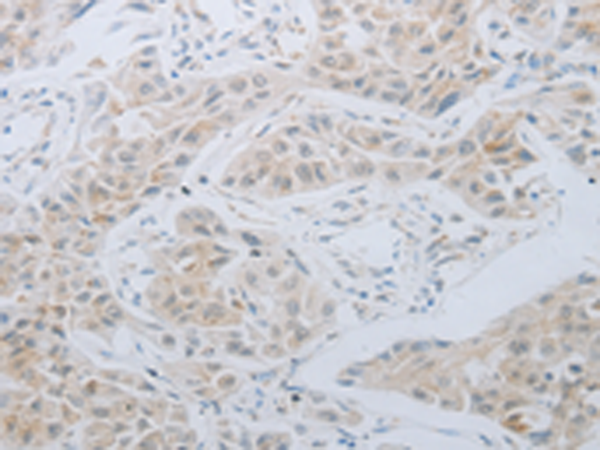

分类: 科研抗体货号: P10690别名: TIM; KIM1; TIM1; CD365; HAVCR; KIM-1; TIM-1; TIMD1; TIMD-1; HAVCR-1应用: WB,IHC反应种属: Human